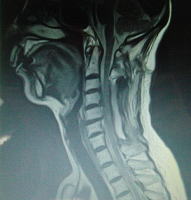

| 手術後の画像 |

ボルトの入った 状態の画像と 思うのですが? |